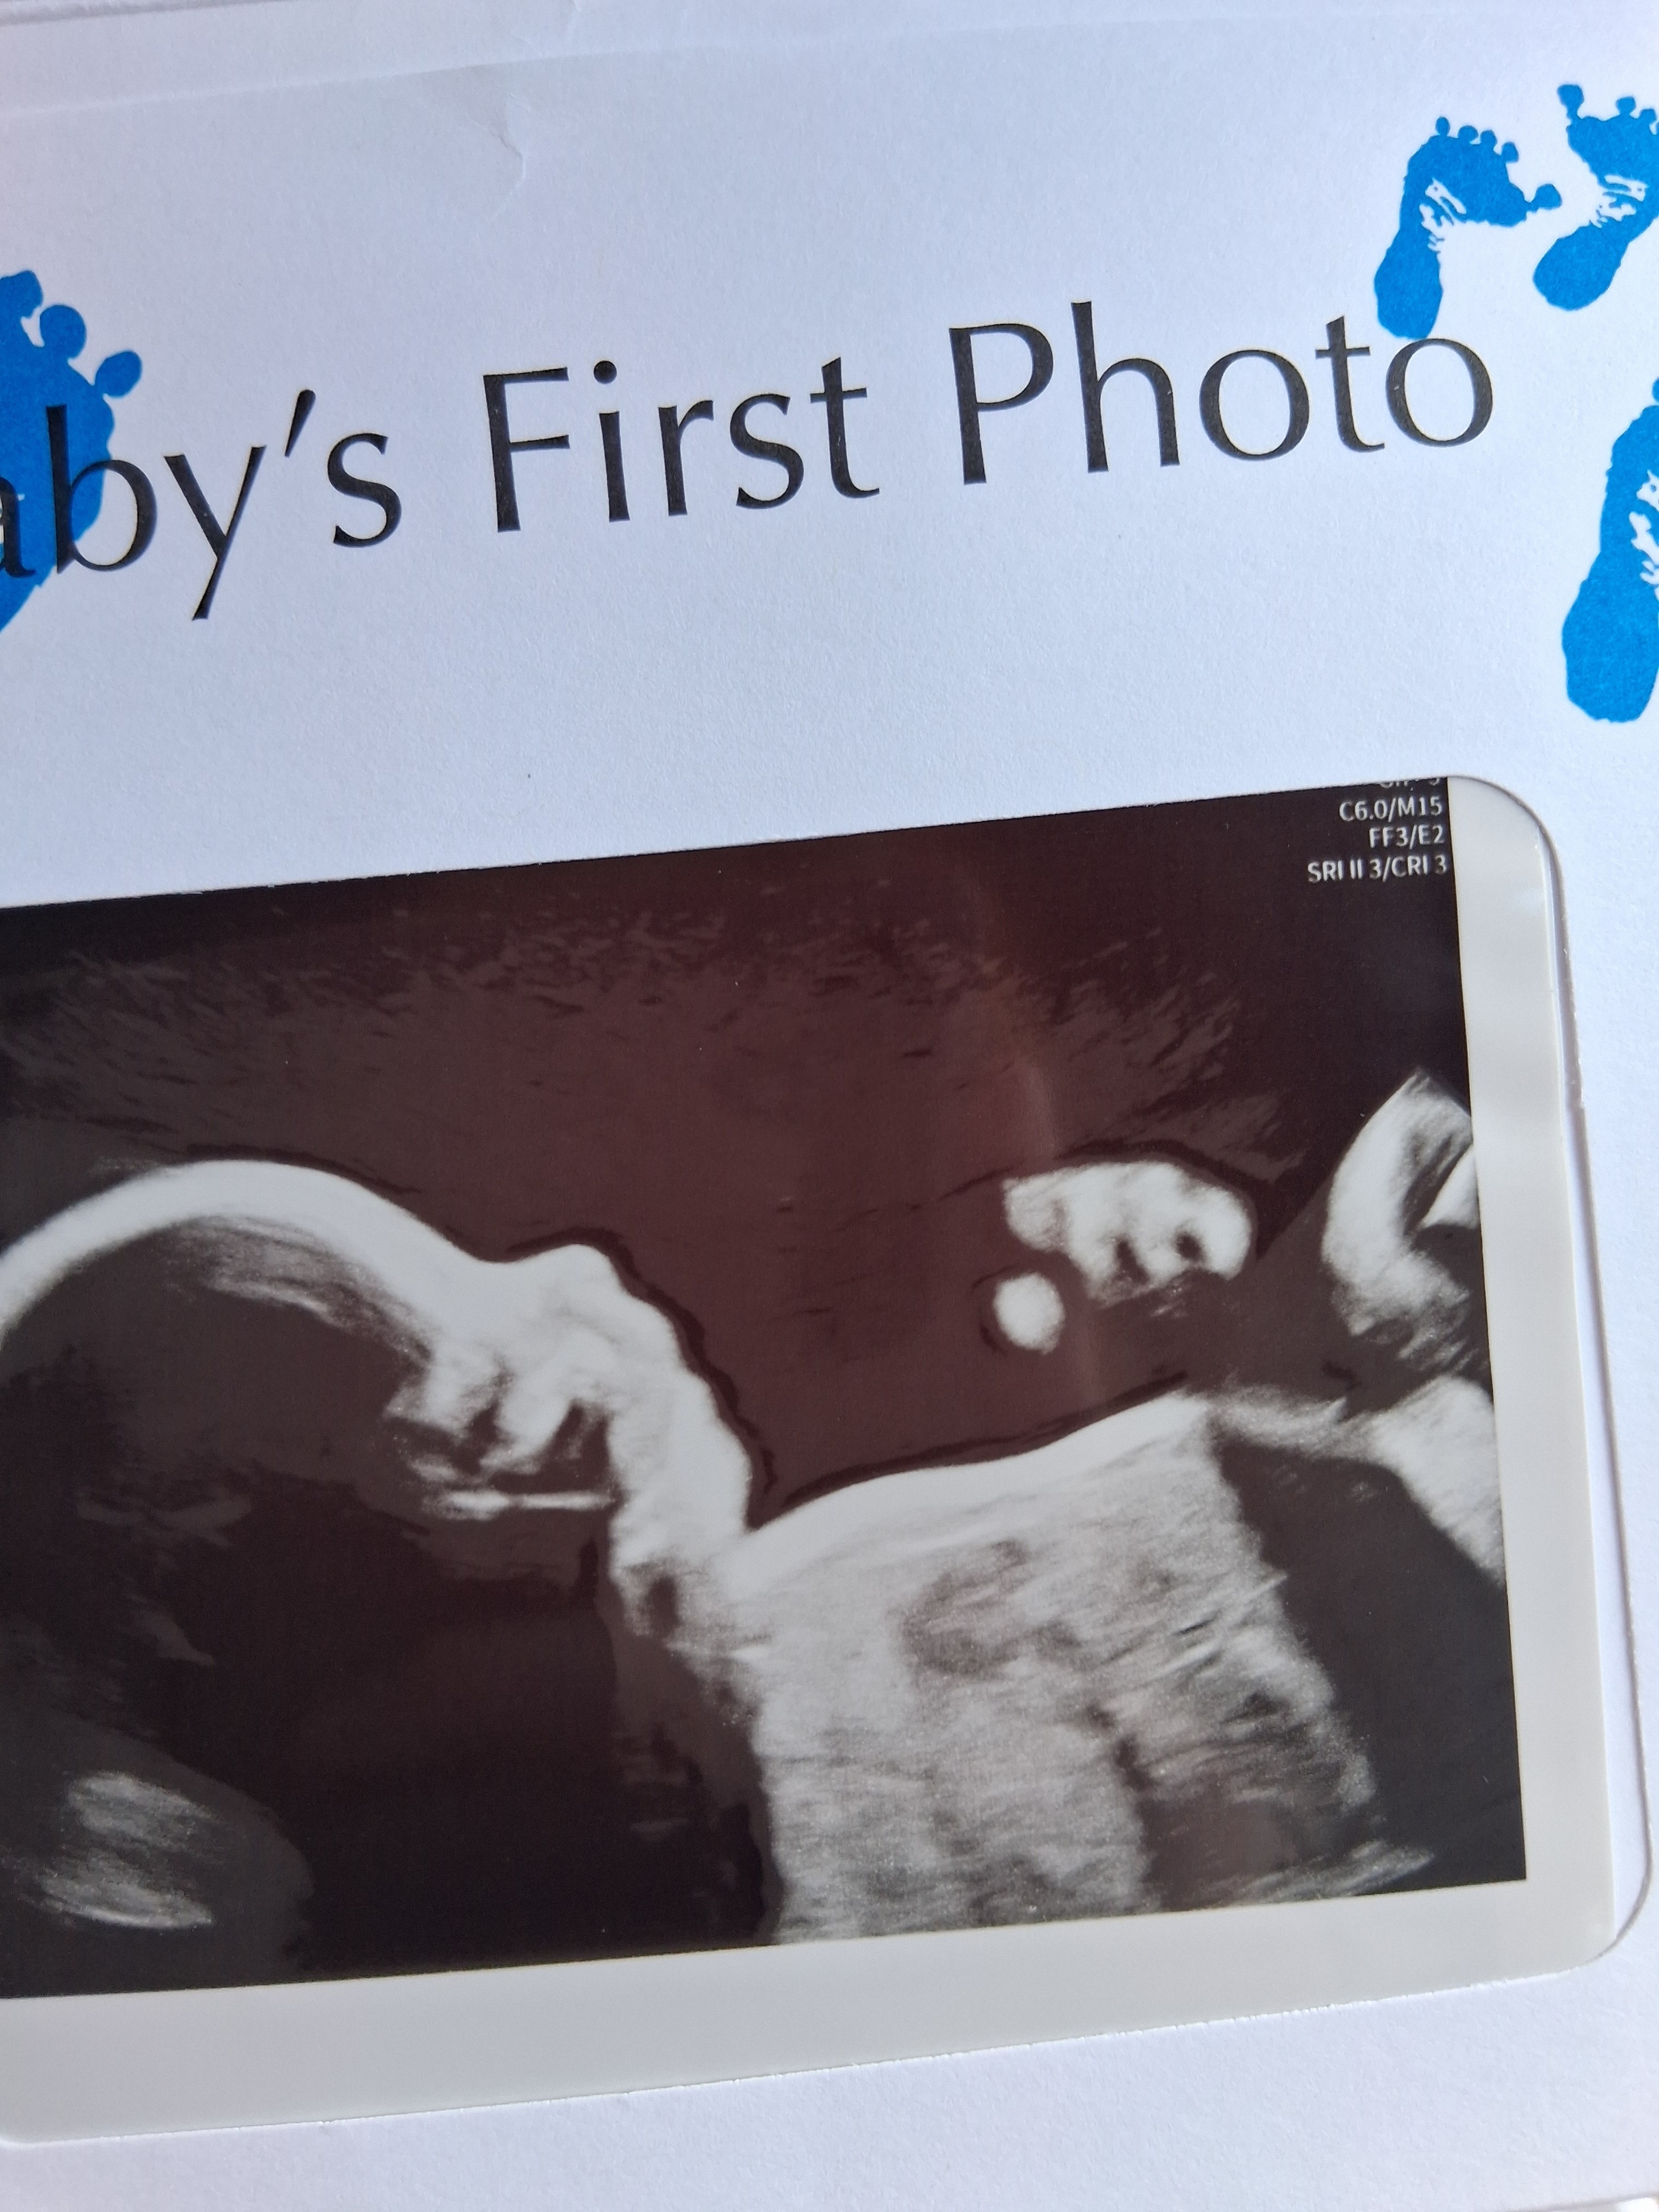

Dean Alexander Green was born on Aug 21, 2025 at 11:22am to his mommy, Lucy. We knew he had a tough road ahead of him. His baby heart was incomplete. He was strong though so we pressed on with a beautiful plan for after he was born. We traveled to Texas for better imaging... we moved to Memphis to be close to our doctors just in case. And then suddenly at 38 weeks and 6 days contractions began... at 39 weeks and 1 day we entered the hospital to meet Baby Dean. When he came into this world he was immediately swarmed with our love. Our hearts full and prepared for the uphill road we were about to face. But Baby Dean was struggling to breath on his own so the hospital did everything they could to help him breath. Baby Dean left this world Aug 21, 2025 at 9:49 pm.